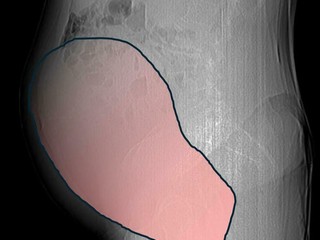

Per mesi la gigantesca cisti ovarica, con un diametro di circa 28 centimetri, è rimasta nascosta, senza dare segnali evidenti. La paziente non si era accorta di nulla. L’allarme è scattato quando la massa, associata alla presenza di una seconda neoplasia intestinale, ha iniziato a comprimere il colon, provocando sintomi acuti ed improvvisi fino ad una grave difficoltà intestinale non più ignorabile.

Fondamentale in questa fase il contributo della Radiologia dell'ospedale Sant’Anna, che fornisce l’imaging preoperatorio indispensabile per affrontare un quadro clinico di eccezionale complessità.

Durante l’intervento emerge tutta la gravità della situazione. La gigantesca neoplasia ovarica viene asportata: pesa circa 6 chilogrammi, con un volume paragonabile a quello di una gravidanza gemellare a termine. Ma non è l’unica minaccia. I sintomi più pericolosi sono legati alla sofferenza intestinale, che richiede un intervento immediato e coordinato di più specialisti.